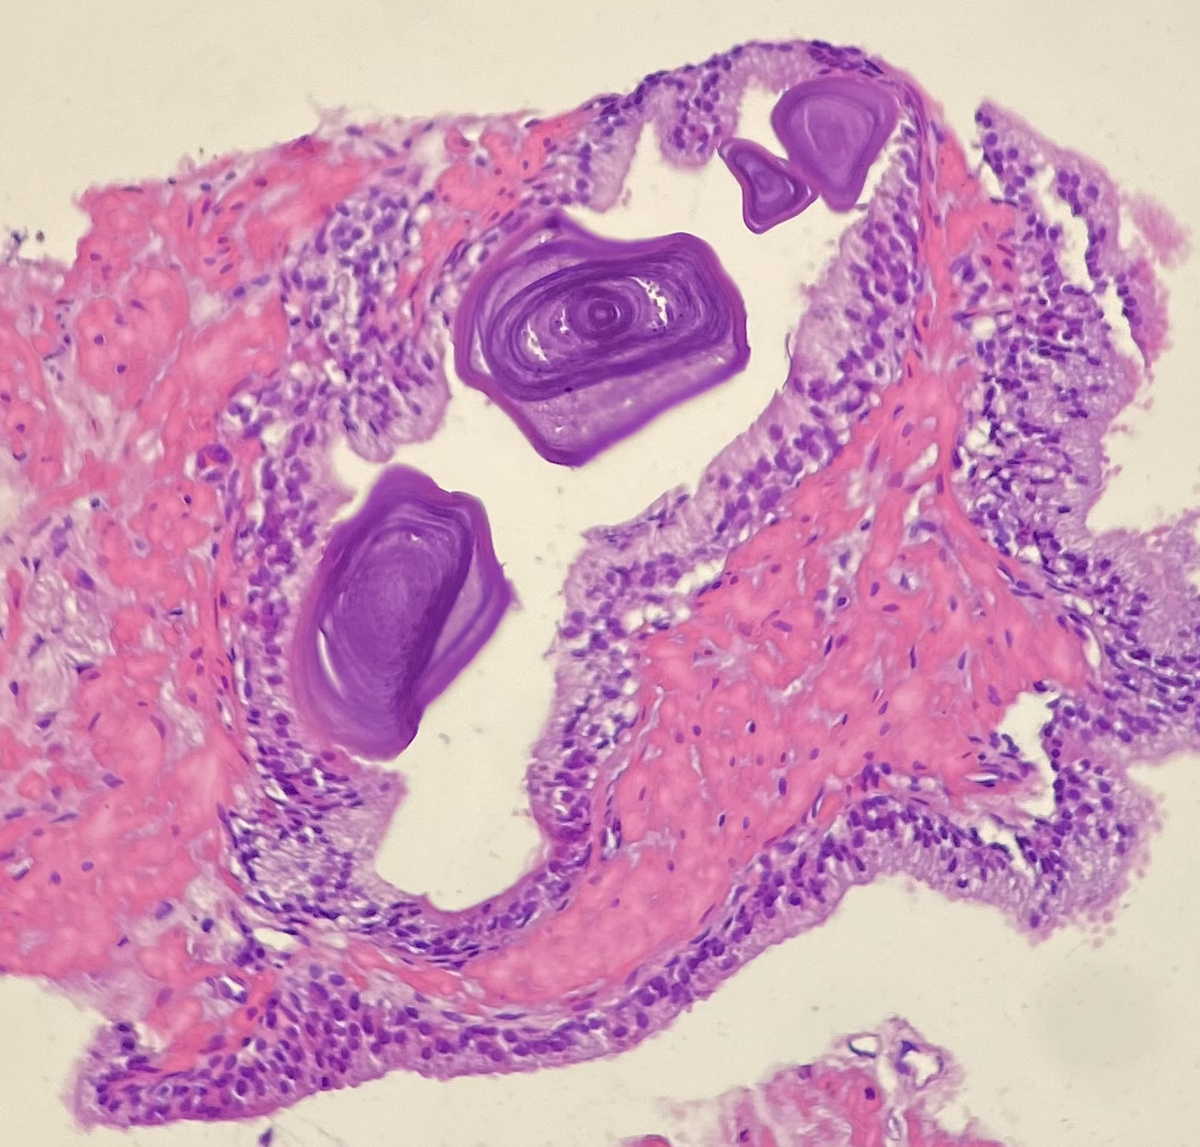

Фрагмент простаты с амилоидными тельцами (как цветочки).